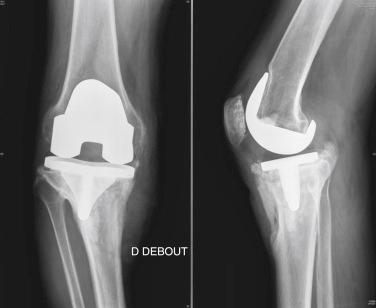

A 70-year-old man underwent a TKA 6 months before referral to our center. He was never satisfied with the results because of persistent pain. Prosthetic loosening with tibia subsidence was observed after 6 months ( Fig. 35.3 ). The result of a perioperative aspiration was negative, but the clinical history supported a diagnosis of chronic infection.

FIGURE 35.3, Case 2: Standard preoperative radiographs. A, Anteroposterior view. B, Lateral view.